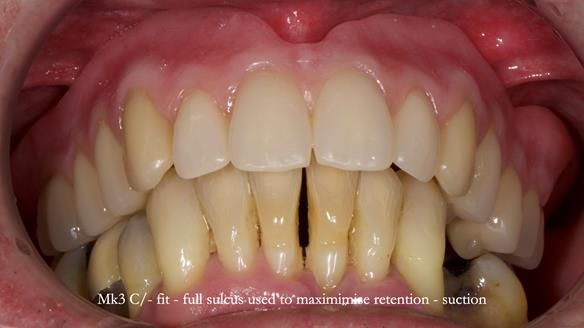

Twelve months after the final extractions, I made the Mk3 definitive complete upper denture.

Three months after fitting, a reline was carried out to adapt to tissue changes from the canine and molar extractions.

For the Mk3, we embedded the metal base fully within the fitting surface acrylic. This design allowed adjustment of the polished surface using universal marking spray to fine-tune sibilance and prevented any join between the metal and acrylic from being felt by the tongue.

This approach solved most (but not all) of the speech issues.

- Retention, stability and support were excellent.

- Speech was good but not perfect.

- Aesthetics were excellent and Jeremy was very happy with this apspect.

- Sibilance with S’s was still a bit of a problem for him, however, Claire (my nurse) and I could not hear problems with the speech.

- Biting and chewing were no problem at all.